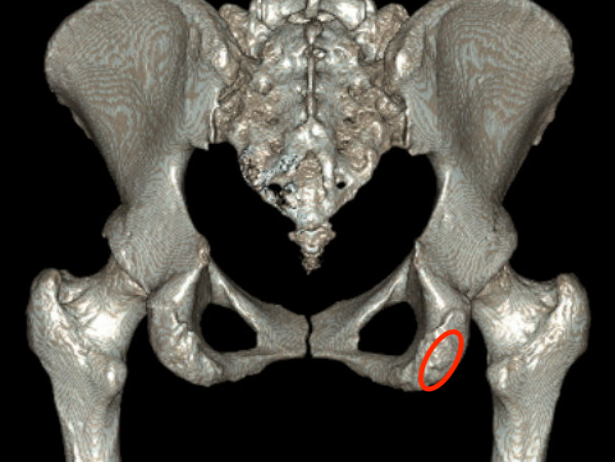

Xray

Exclude bony avulsion

Proximal hamstring avulsion on right - red circle is retracted hamstring tendon, blue circle is normal insertion on left